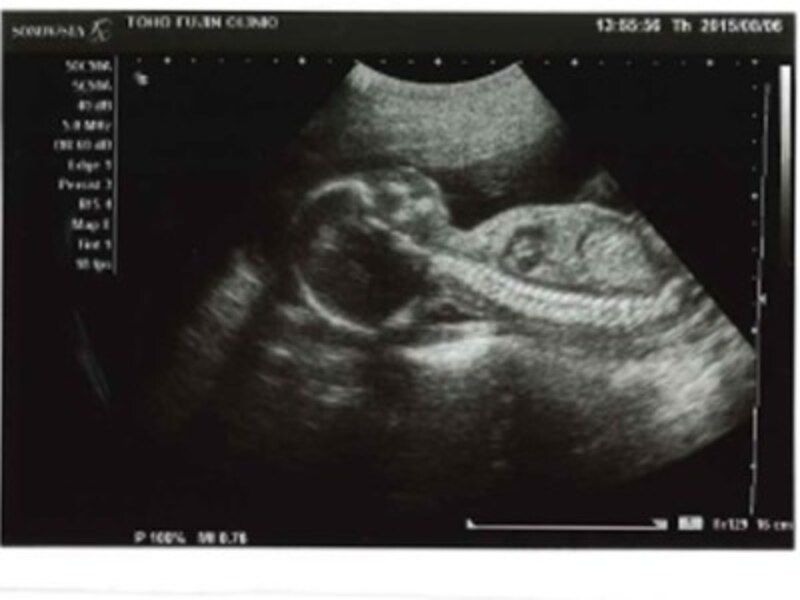

妊娠 17 週から 20 週の間に、超音波画像で確認できる先天性異常がないか胎児を評価するために、レベル 1 の超音波検査が完了します。異常な所見があれば、レベル 2 のスキャンが行われる場合があります。